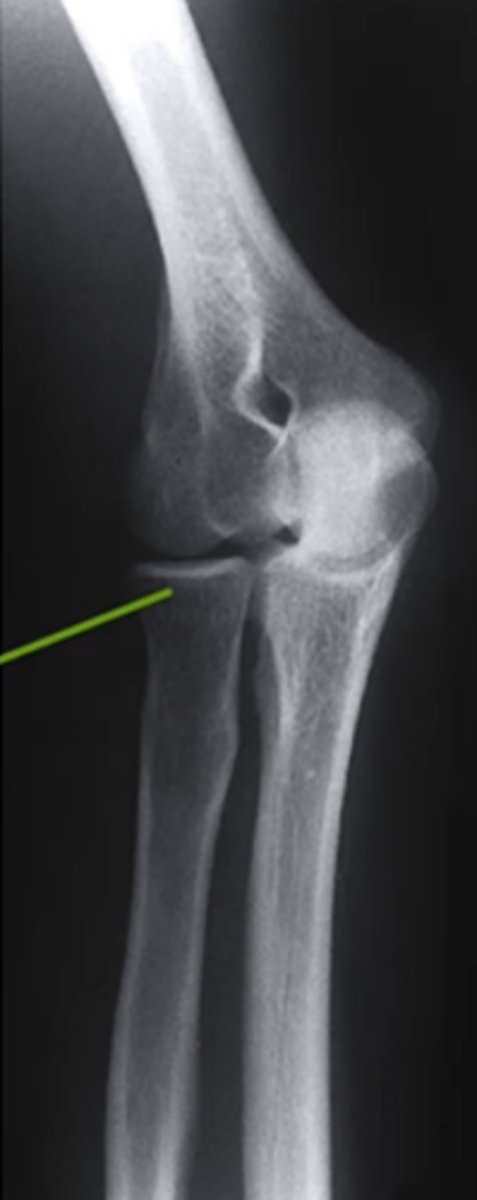

AP Elbow

what view is this

lateral epicondyle

what does the pink line point to?

medial epicondyle

Capitulum

coronoid process

shaft of ulna

shaft of the radius

radial tuberosity

radial head

radial neck